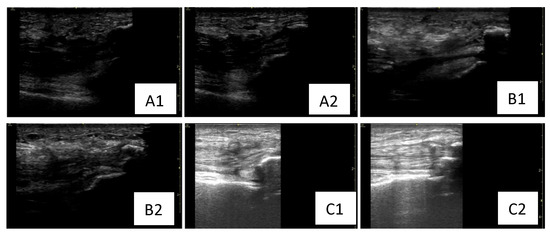

Serial dynamic musculoskeletal ultrasound assessments were performed at admission and at 6 and 9 weeks postoperatively by a single experienced physiatrist to ensure consistency and eliminate inter-rater variability. Standard musculoskeletal ultrasound settings were applied, with the gain adjusted between 40 and 60 dB to optimize tendon and muscle visualization in both longitudinal and transverse views during dynamic assessment of the quadriceps tendons. Moreover, along with other physiatrists who also were part of the rehabilitation team of our patient, based on clinical and ultrasound findings, we made real-time decisions for the rehabilitation program. The reasoning behind dynamic musculoskeletal ultrasound is that this valuable tool is non-invasive, repeatable, and enables real-time feedback to adjust rehabilitation based on objective findings such as tendon continuity and healing status, structural integrity (e.g., fibrillar pattern, scarring), muscle activation during motion, tendon glide and contractility, effusion or post-surgical complications (e.g., hematoma, adhesions) [10,11,12]. All these features were taken into consideration for every step of the rehabilitation program and helped adapt the program in real-time, allowing a tailored intervention according to the patient’s post-surgical and rehabilitation stage. Literature findings highlight novel ultrasound-guided rehabilitation strategies and demonstrate how imaging can be used dynamically to guide treatment and decision-making, reinforcing the role of ultrasonography in musculoskeletal rehabilitation pathways [13]. A literature review contextualizes ultrasound findings in chronic tendinopathies and supports the utility of imaging follow-up and real-time adjustments in accordance with tendon and muscle architecture changes, while reinforcing our approach towards dynamic sonographic monitoring in the case of our patient, notably in chronic conditions such as long-term gout and diabetes, which frequently impact tendon structure [14]. The rehabilitation program was tailored according to muscle and tendon appearance, inflammation and recovery, aiming to provide a real-time strategy adapted to the musculoskeletal needs of the patient for each rehabilitation phase. Figure 4 highlights different bilateral sonographic assessments of quadriceps tendon at different time points (T0, T1, T2) presenting architectural and inflammatory changes. At baseline assessment (T0), the quadriceps tendon had lost the fibrillar aspect and demonstrated a thickened pattern as well as the presence of edema. According to the sonographic findings, the rehabilitation program focused on pain management, wound healing, surgical protection, the maintenance of ROM, muscle strength, and overall function. LLLT was also applied to decrease inflammation and assist healing. The musculoskeletal ultrasound at 6 weeks post-surgery revealed a relatively homogeneous, echogenic left and right quadriceps tendon with fibrillar pattern, several peritendinous calcifications and reduced subcutaneous tissue edema compared to the baseline evaluation. Correlating these findings with the clinical assessment, we started the second rehabilitation phase (weeks 5–7), and the braces were removed at week 6 post-surgery. We continued the passive mobilization and also began active muscle strengthening. By the end of the post-surgical rehabilitation program (week 9), the quadriceps tendon had regained homogeneity and its fibrillar aspect and the subcutaneous tissue edema was resorbed. Therefore, progressive strengthening, walking on even and uneven surfaces, and stair training were initiated for our patient. We aimed to use serial ultrasound to better adapt the post-surgical rehabilitation plan to the patient’s needs while considering the tendon appearance and edema level. Considering the ultrasonographic changes of tendons and muscles and adapting the rehabilitation program accordingly led to setting active goals in rehabilitation and facilitate recovery through increased speed rate and better outcomes at discharge and follow-up.

Figure 4. Serial dynamic sonography for left and right lower limbs assessed at different time points (T0, T1, T2) post-surgery. (A1,A2) Relatively non-homogeneous, hypoechoic left and right quadriceps tendon with loss of fibrillar pattern and thickened appearance, associated with the presence of peritendinous calcifications and subcutaneous tissue edema (baseline evaluation). (B1,B2) Relatively homogeneous, echogenic left and right quadriceps tendon with fibrillar pattern, several peritendinous calcifications and reduced subcutaneous tissue edema (sonographic evaluation at 6 weeks post-surgery). (C1,C2) Homogeneous, hyperechoic left and right quadriceps tendon with fibrillar pattern, presenting several peritendinous calcifications and resorption of the subcutaneous tissue edema (sonographic evaluation at 6 weeks post-surgery). T0: baseline sonographic assessment at admission; T1: sonographic assessment at 6 weeks post-surgery.; T2: sonographic assessment at 9 weeks post-surgery (at discharge).